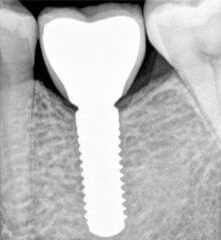

Проблема. Удаление коренного зуба.

Решение. Через 3 месяца, после заживления кости, установлен зубной имплантат и сразу же прикреплена заживающая головка.

Через 2,5 месяца, после приживления имплантата, установлена постоянная коронка.